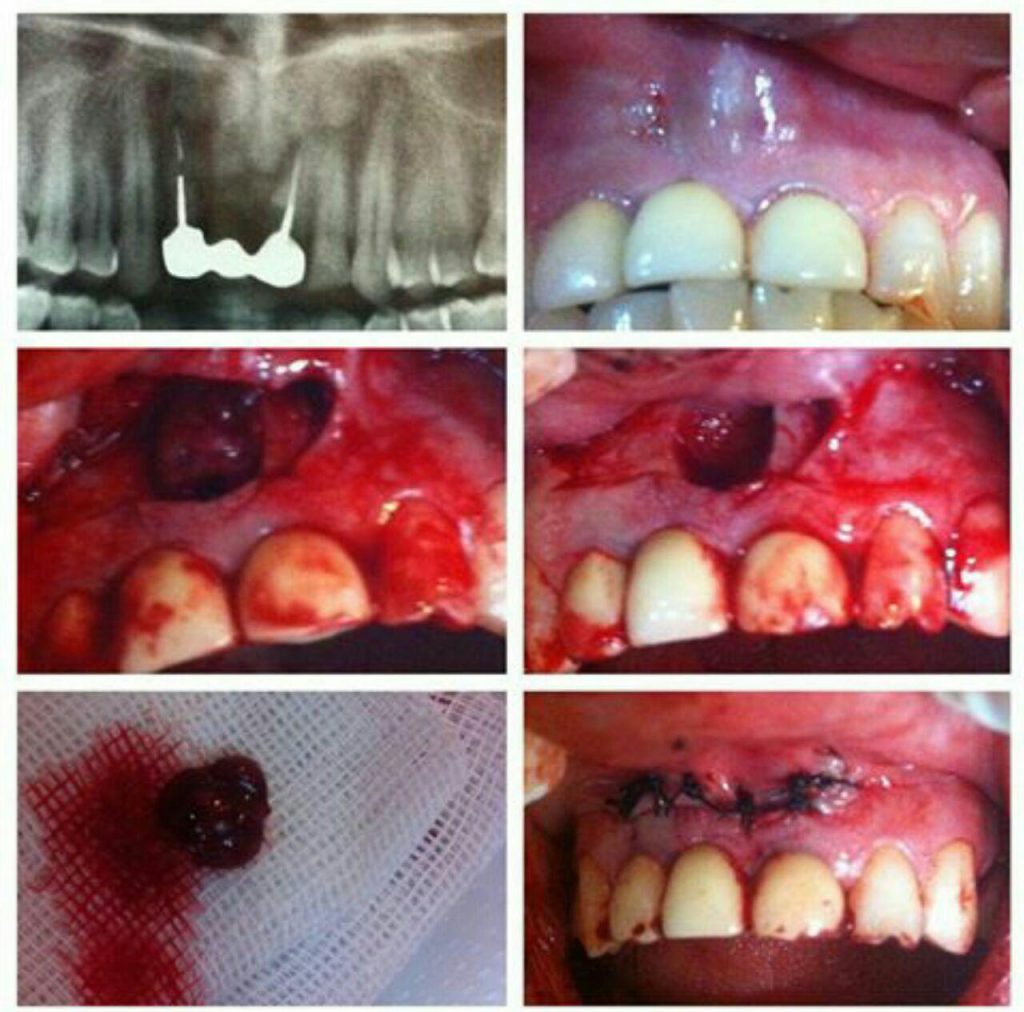

كلينيك تخصصي دندانپزشكي دكتر حامد كرامت

جراح دندانپزشك

متخصص بيماريهاي دهان، فك و صورت

فلوشيپ ايمپلنت از ICOI آمريكا

گواهينامه ايمپلنت و زيبايي از دانشگاه UCLA آمريكا